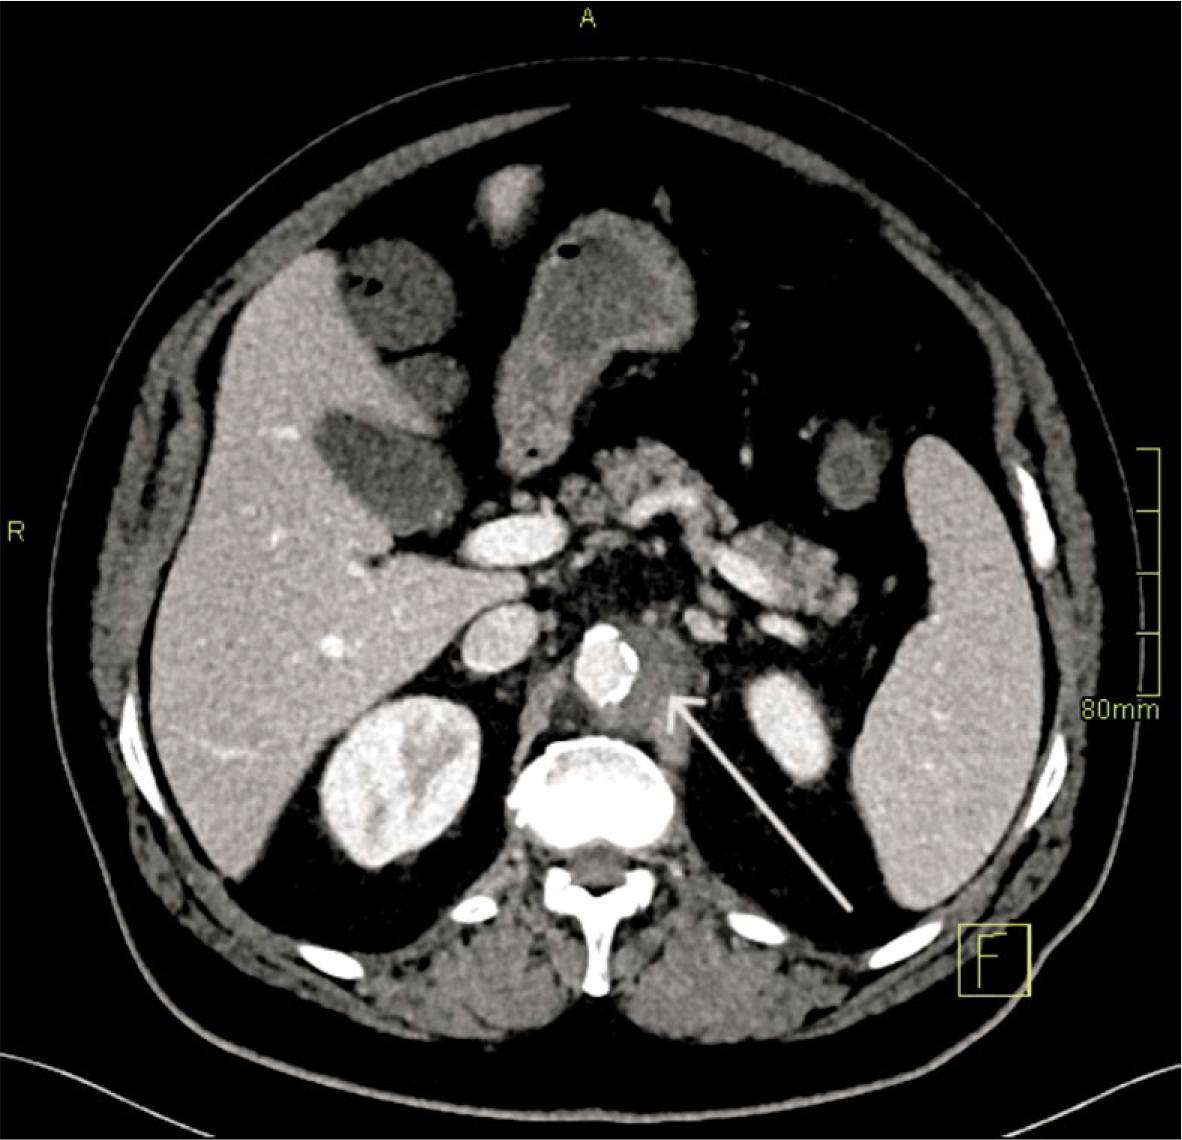

FIGURE 1.